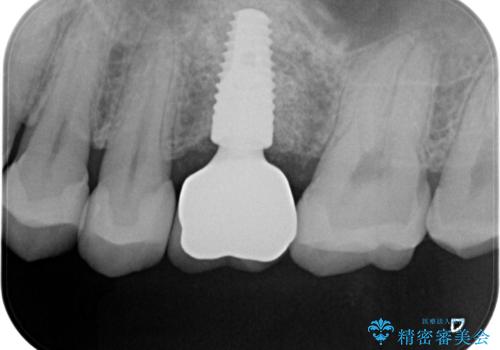

- 左上6:歯槽堤保存術/110,000円 サイナスリフト/110,000円 骨造成/55,000円 静脈内鎮静/55,000円 インプラント体/242,000円 チタンカスタムアバットメント/110,000円 仮歯/22,000円 ジルコニアクラウン/121,000円 合計825,000円 左上5:セラミックインレー/77,000円費用は治療当時の料金となります

良い位置に良い方向でインプラントを埋入することができました。

手前の歯の虫歯もセラミックインレーで精度よく治療を行いました。